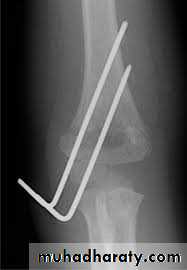

Surgery

Hand deformity